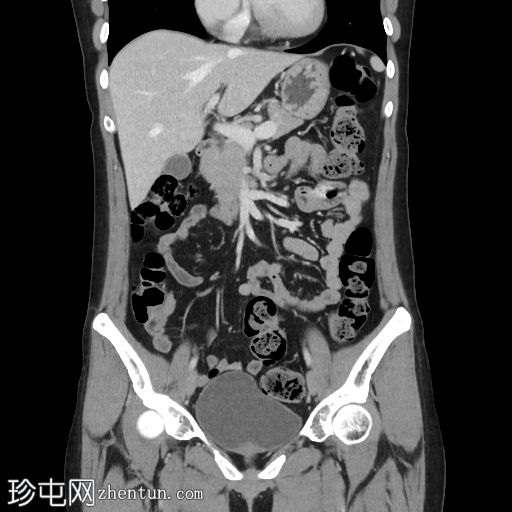

7.jpg

门静脉期

冠状面C+期

8.jpg

延迟

在轴向、冠状面和矢状面上均可见肝5/6段病变。动脉期可见周围结节状强化,门静脉期可见进行性向心性充盈,延迟期亦持续存在。这些表现为肝血管瘤的特征性表现。

然而,目前的CT扫描显示动脉期呈周围结节性强化,门静脉期呈进行性向心性充盈,且延迟成像后仍持续存在。这些特征是肝血管瘤的特征。未发现其他肝脏病变。